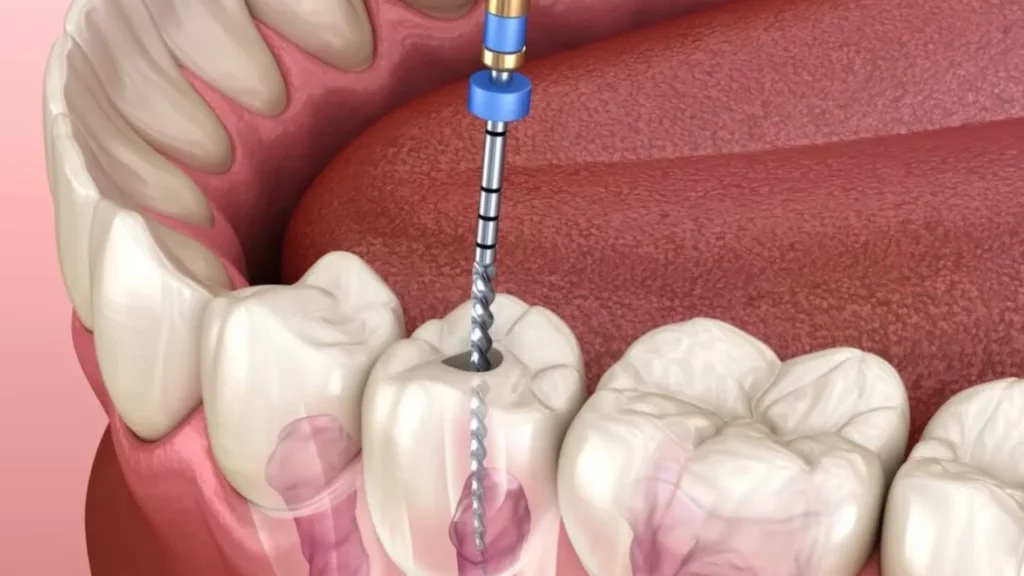

Modern treatment of chronic pulpitis focuses on advanced techniques designed to preserve the tooth whenever possible and provide rapid, safe pain relief. The process begins with precise diagnosis, often using CBCT 3D imaging to accurately determine the extent of damage to the pulp and root canals.Root canal therapy performed under an operating microscope and with the aid of dental lasers is among the latest approaches. These technologies allow the dentist to clean the root canals with great precision, thoroughly disinfect them, and remove the bacteria responsible for the chronic infection while maintaining as much of the tooth structure as possible.In advanced cases of chronic pulpitis, retreatment of a previous root canal or an apicoectomy (surgical removal of the root tip) may be necessary to save the tooth instead of extracting it. Modern biocompatible root filling materials are used to support healing of the bone around the roots and reduce the risk of reinfection. If the tooth cannot be saved, extraction followed by replacement with a dental implant or a fixed bridge becomes the final treatment option, with careful attention to addressing the underlying causes of chronic pulpitis to prevent similar problems in other teeth.